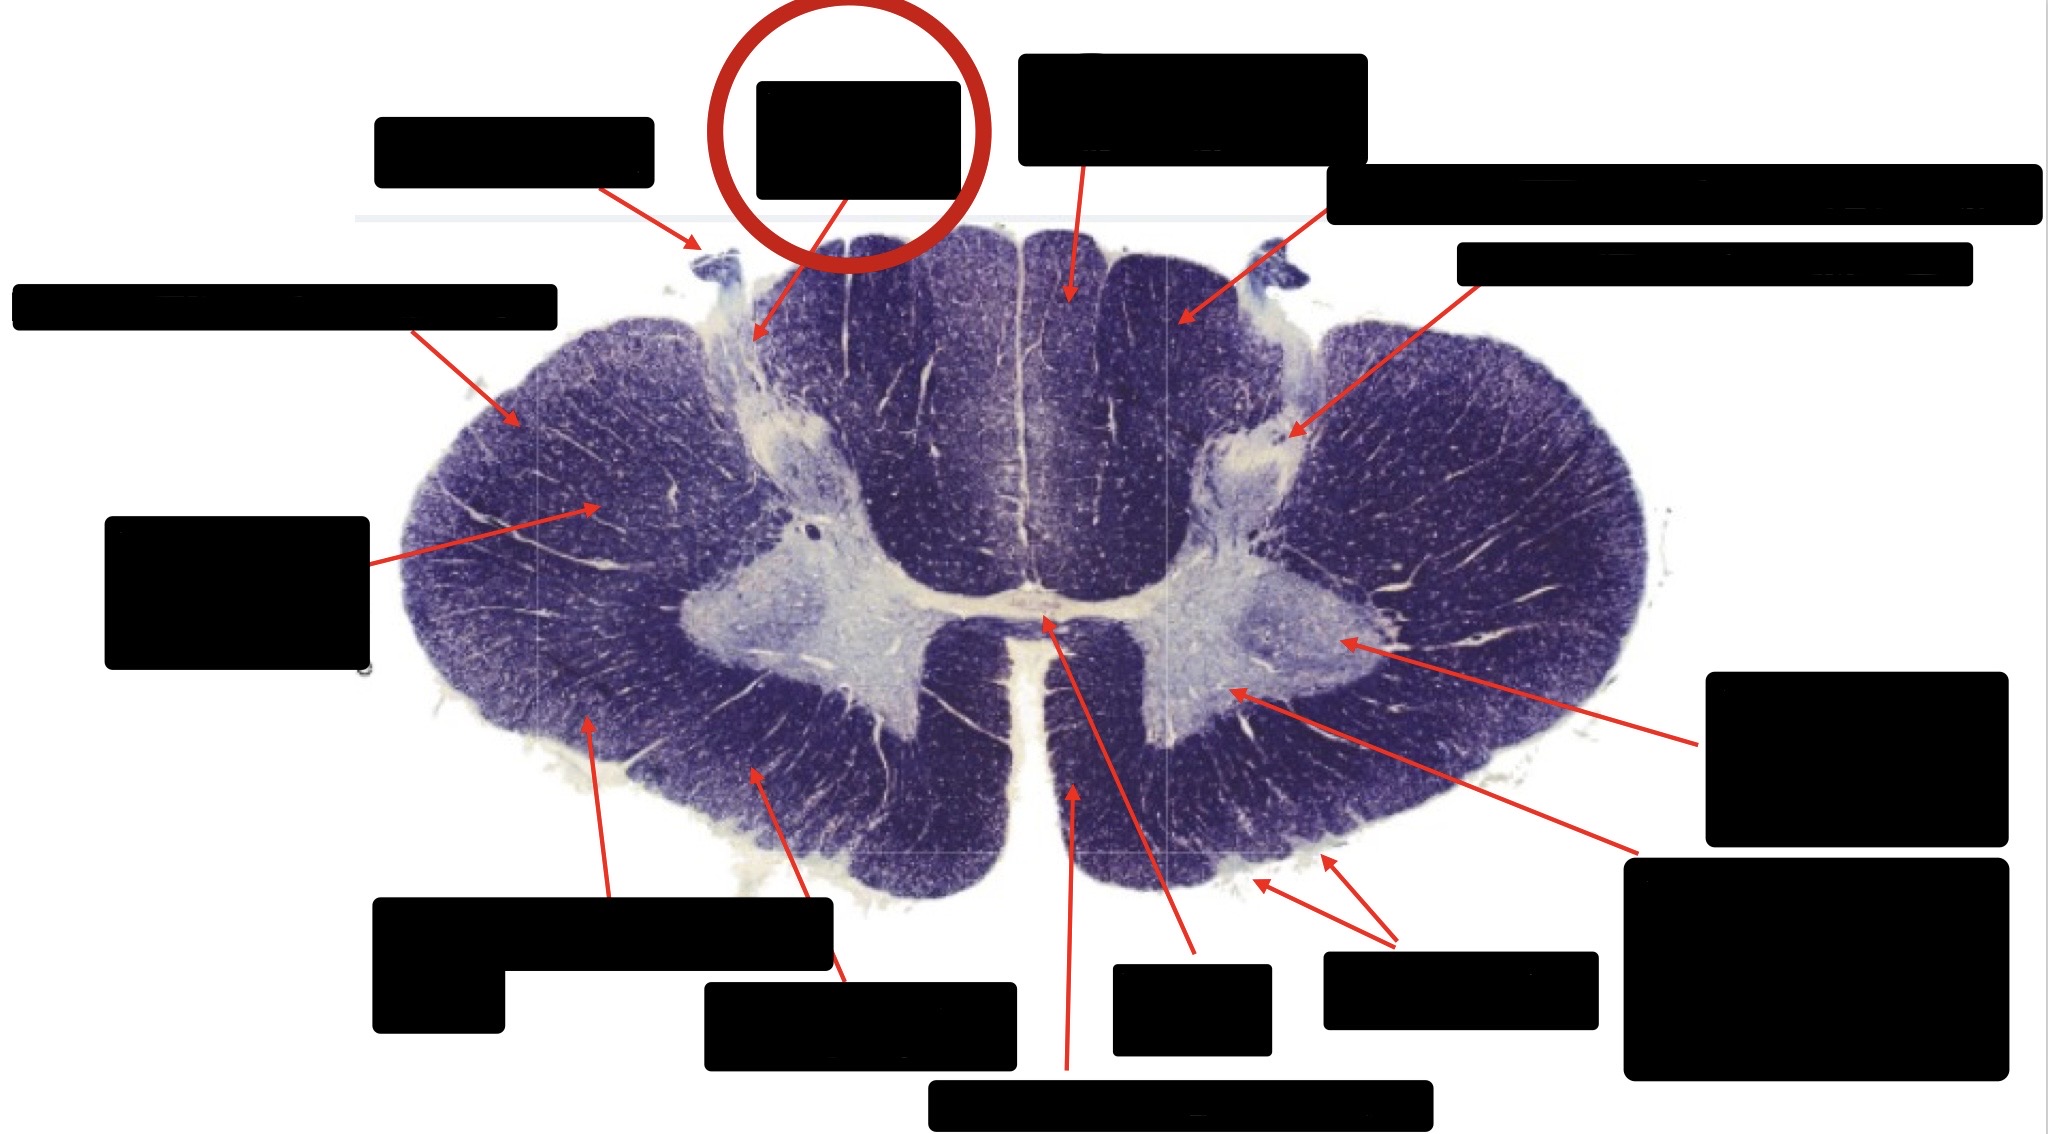

Anterior Spinal Artery

Denticulate Ligament

Ventral Root

Dorsal Root

Posterior Column Fasciculus Gracilis

Large Fiber Entry Zone

Central Canal

Dorsal Rootlet

Lissaeur’s Tract & Small Fiber Entry Zone

Substantia Gelatinosa

Lateral Corticospinal Tract

Anterior Horn Motor Neuron

Spinothalmic Tract

Anterior Horn Motor Neurons